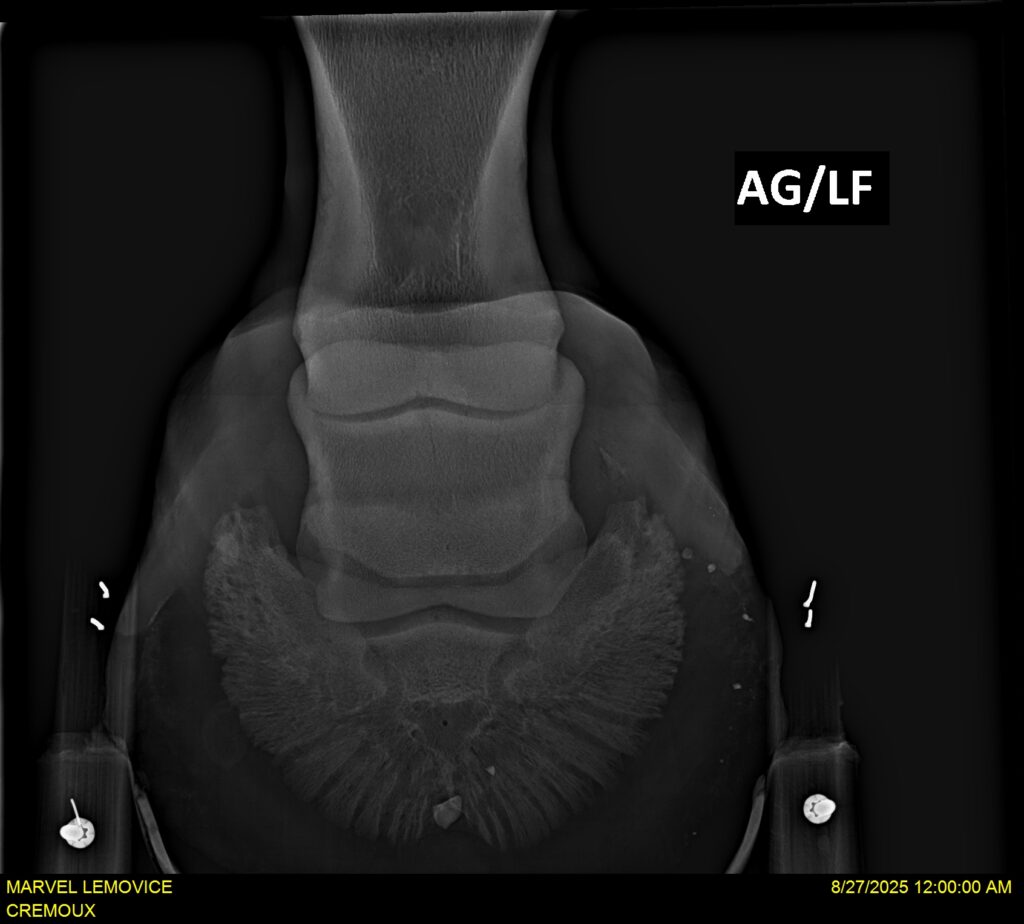

MARVEL LEMOVICE, hongre, Selle Français prend 4 ans en 2026. POPSTAR LOZONAIS x ROSIRE sur une excellente souche maternelle de l’élevage PLATIERE. Débourré aux trois allures et mise en route à l’obstacle. Super modèle avec du cadre et de la force, cheval respectueux avec des moyens. Très agréable au quotidien. Transport OK, maréchalerie OK, santé RAS, Bilan 20 clichés radios + clinique OK.

RADIOS ET CLINIQUE